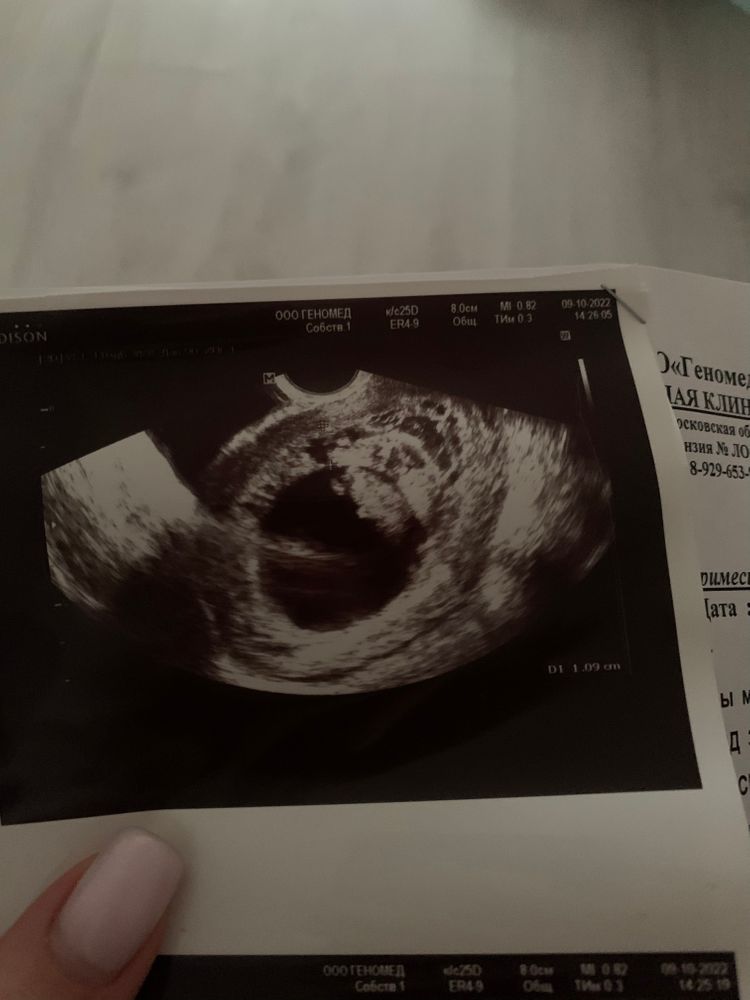

Пузырный занос. Узи. Помогите разобраться, если кто-то понимает🙏

Врач говорит похоже на начало частичного пузырного заноса.

10 неделя, беременность развивается, эмбрион жив.

кто как либо сталкивался с такой проблемой, прошу посмотрите узи!

фото прикрепляю. Буду очень благодарна любому мнению. Спасибо